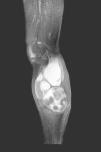

Fig. 4.

MR. Sagittal STIR image. The hematoma shows diffuse increased signal intensity.